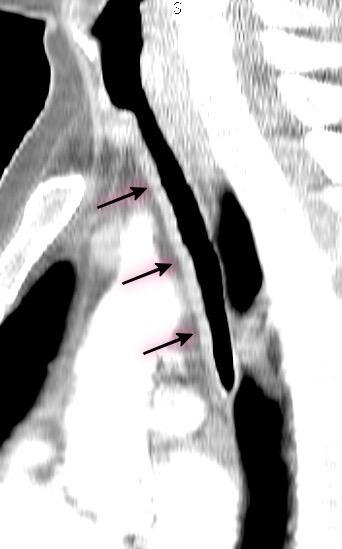

1/300 autopsias. Broncoscopia ..0,7%.

5ª-6ª décadas. + Varones.

2/3 inferiores de tráquea y bronquios principales. Sólo pared anterior y laterales. + Asintomáticos

Prince JS et-al. Nonneoplastic lesions of the tracheobronchial wall: radiologic findings with bronchoscopic correlation. Radiographics. 2002/ Shrof GS et al. Pathology of the Trachea and Central Bronchi. Semin Ultrasound CT MRI 2016